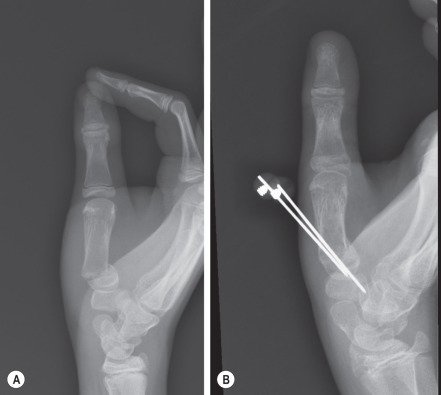

Examples of appropriate K-wire used include displaced but reducible fractures throughout the phalanges and metacarpals that can be aligned, but are unstable. These can include articular fractures that must maintain a near anatomical orientation, fractures with a sharp obliquity pattern that can lead to proximal migration, or nonarticular fractures in close proximity to a joint that can create a great deal of stress at the fracture site ( Figs. 5.7.2 and 5.7.3 ).